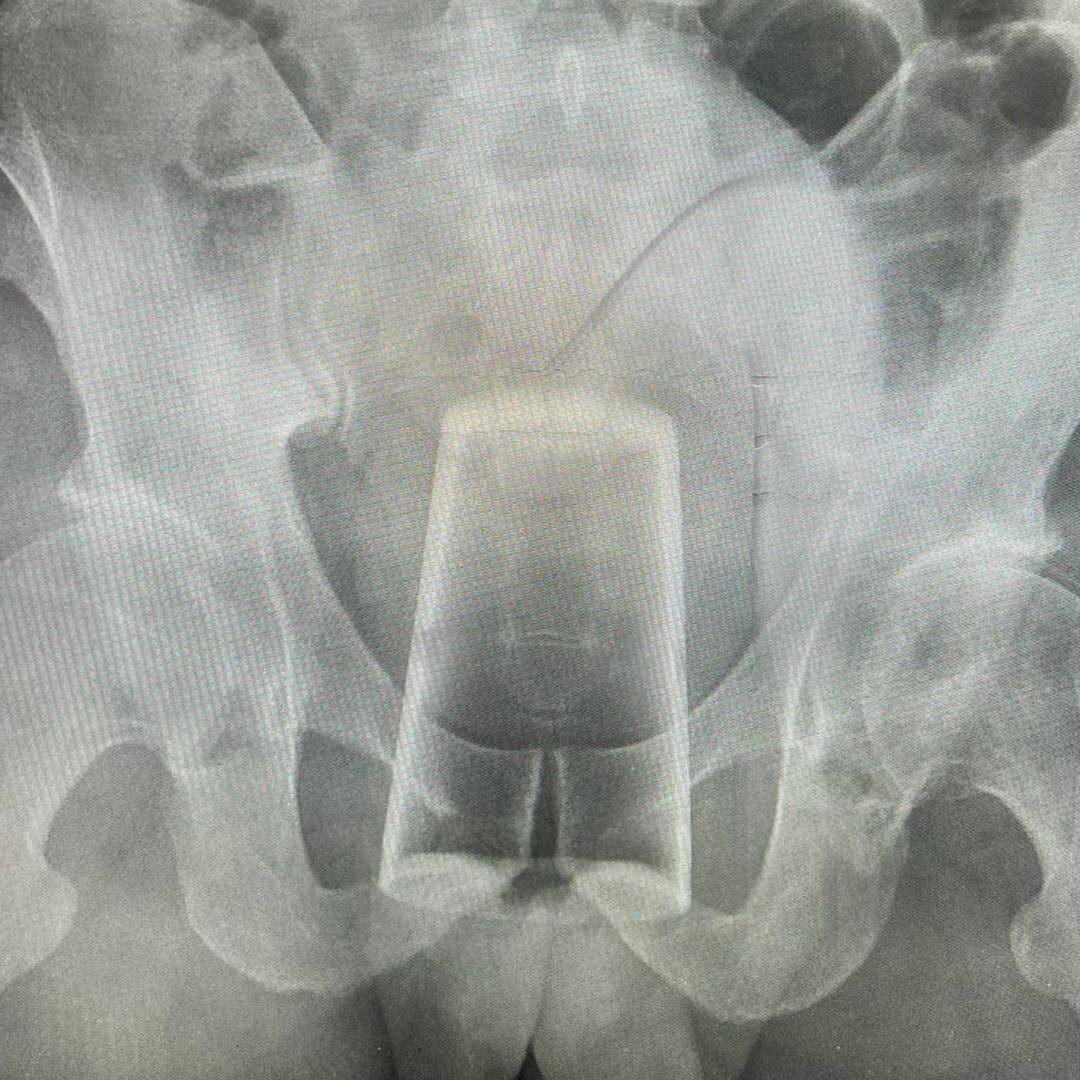

Стакан застрял в заднем проходе мужчины после празднования 23 февраля в Уфе

Стакан застрял в заднем проходе мужчины после празднования 23 февраля в Уфе. По словам пострадавшего, они с товарищем выпили и решили устроить некий конкурс. В какой-то момент мужчина поскользнулся и упал, в результате стакан глубоко проник в прямую кишку.

Вытащить инородное тело самостоятельно не получилось, поэтому пострадавшему пришлось вызвать бригаду скорой помощи. Мужчине провели операцию и отпустили домой.